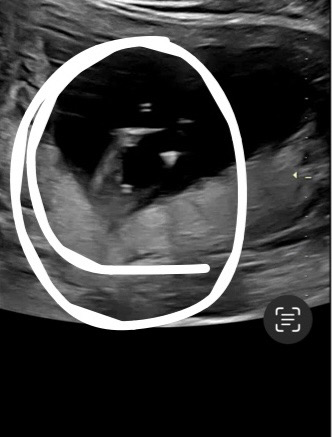

이거 혹시 🌶️인가요..?

아직 성별 모르는 13주차입니다 ! 12주때꺼 초음파 다시 보다가 혹시..? 라는 생각이 들어서용 투표부탁드려요☺️